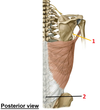

1? 2?

1: Teres major muscle

2: Latissimus dorsi muscle